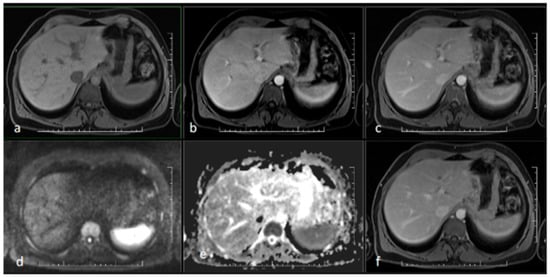

At this stage, initial pretransplant results were obtained, surprisingly showing positive serological results for syphilis. Both a rapid plasma reagin test (RPR) (1:32 titer) and the Treponema pallidum particle assay test (TPPA) (1:38) turned out positive and confirmed the diagnosis of syphilis. As Treponema pallidum is known to be a causative agent of secondary sclerosing cholangitis, further pretransplant examinations were discontinued, and empirical causative therapy was initiated with procaine benzylpenicillin at a daily dose of 1.5 million units for 22 days. As a result, serum bilirubin levels and the levels of other hepatic markers decreased significantly and reached normal levels (Figure 2). A follow-up MRCP after 3 months showed only minor residual changes in the intrahepatic ducts of the left lobe, suggesting an almost complete cure (Figure 3 and Figure 4).

Figure 3. MR scan of the liver after antibiotic treatment: (a) native image; (b) arterial phase; (c) venous phase; (d) diffusion-weighted imaging; (e) ADC map; (f) delayed phase. Narrowing of the originally markedly dilated intrahepatic biliary ducts and regression of pathological opacification are noticeable in the arterial (b), venous (c), and delayed (f) phases. Regression of the pathologic signal was detected in diffusion-weighted imaging (d).